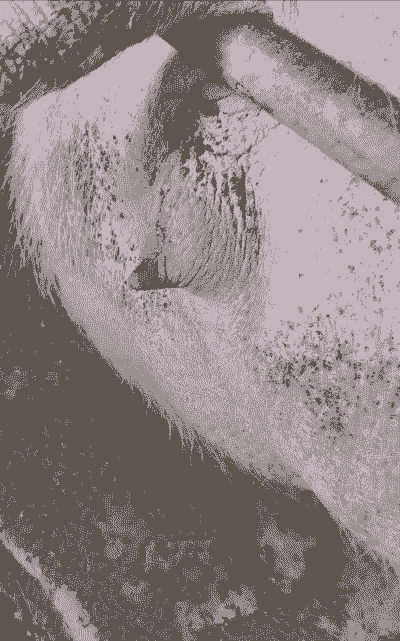

外阴肿胀撕裂

原因:母猪在生产过程中,由于胎儿过大、胎位不正或产道狭窄等原因,可能导致外阴肿胀后破裂或阴户撕裂,从而引起动脉血管断裂,导致大出血。

症状:出血呈喷射状,失血速度快,止血药效果不理想。

外阴肿胀撕裂的救治

初步处理:使用生理盐水清洗出血外阴,手指不断压迫寻找出血位置,一旦找到,用灭菌纱布浸上肾上腺素液(0.1%)进行压迫止血,压迫3分钟后查看,如果止血不住,需要进行缝合。